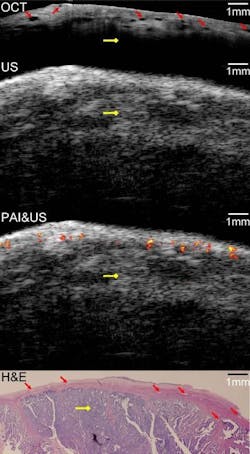

Described by the team in the September issue of Biomedical Optics Express, the diagnostic device combines the contrast provided by photoacoustic imaging, the high-resolution subsurface imaging provided by OCT, and the deeper tissue imaging provided by pulse-echo ultrasound. They tested their device by imaging both pig and human ovarian tissue, and correctly identified malignant tumors that were later confirmed by staining the tissue and examining it under a microscope. These initial tests were performed on tissue that had been surgically removed, but the device's 5 mm diameter is small enough that it could potentially be inserted through a small slit to image tissue in live patients.